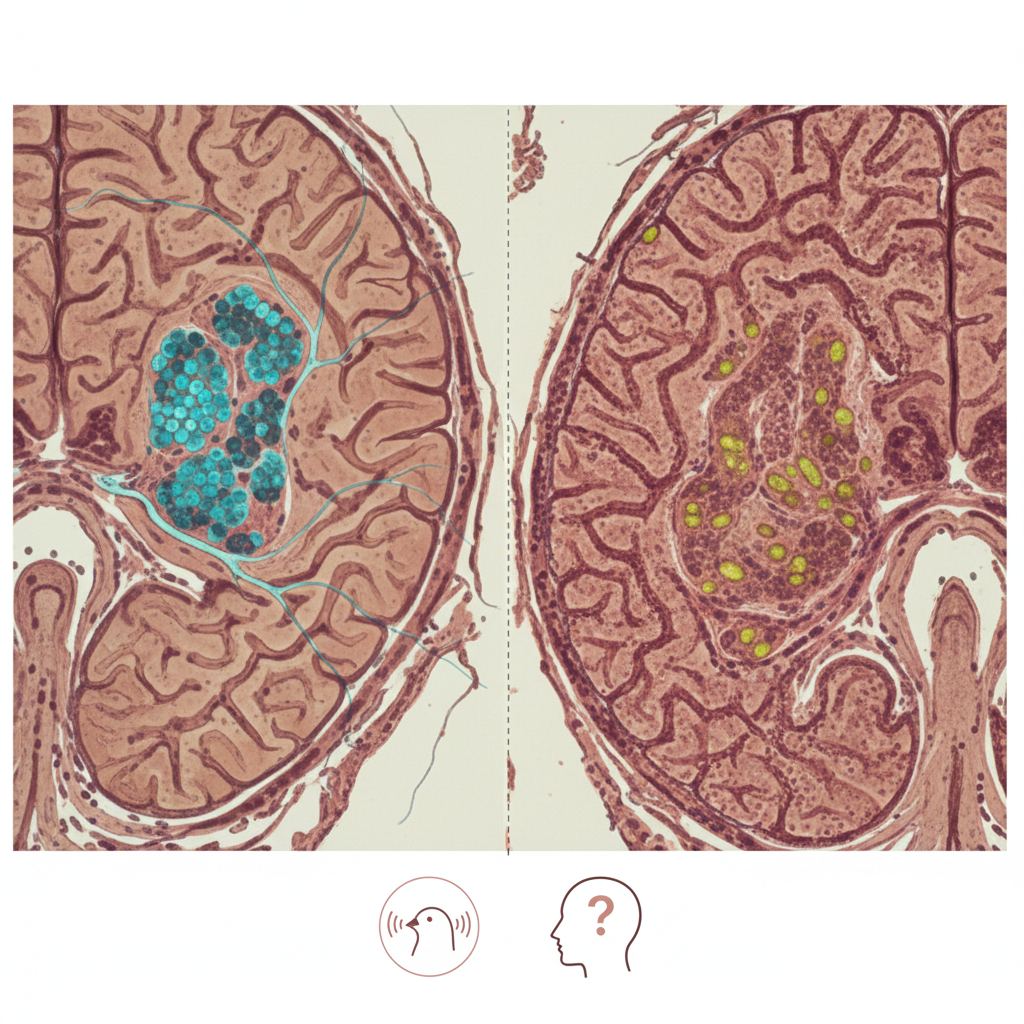

Um dos principais benefícios de Ozempic é sua eficácia em reduzir a hemoglobina glicada (A1c), um indicador crucial do controle glicêmico a longo prazo. Estudos mostram que pacientes que utilizam Ozempic apresentam níveis de glicose mais estáveis, reduzindo o risco de complicações.